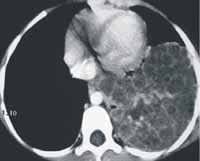

La tomografía computarizada de alta resolución del pulmón mostró imagen heterogénea, localizada en la base izquierda, de 6 por 7 cm, con algunos tabiques, compatible con malformación adenomatoidea quística grado II-III (ver Figura 3).

Figura 3. Tomografía computarizada de alta resolución. Corte transversal y corte coronal